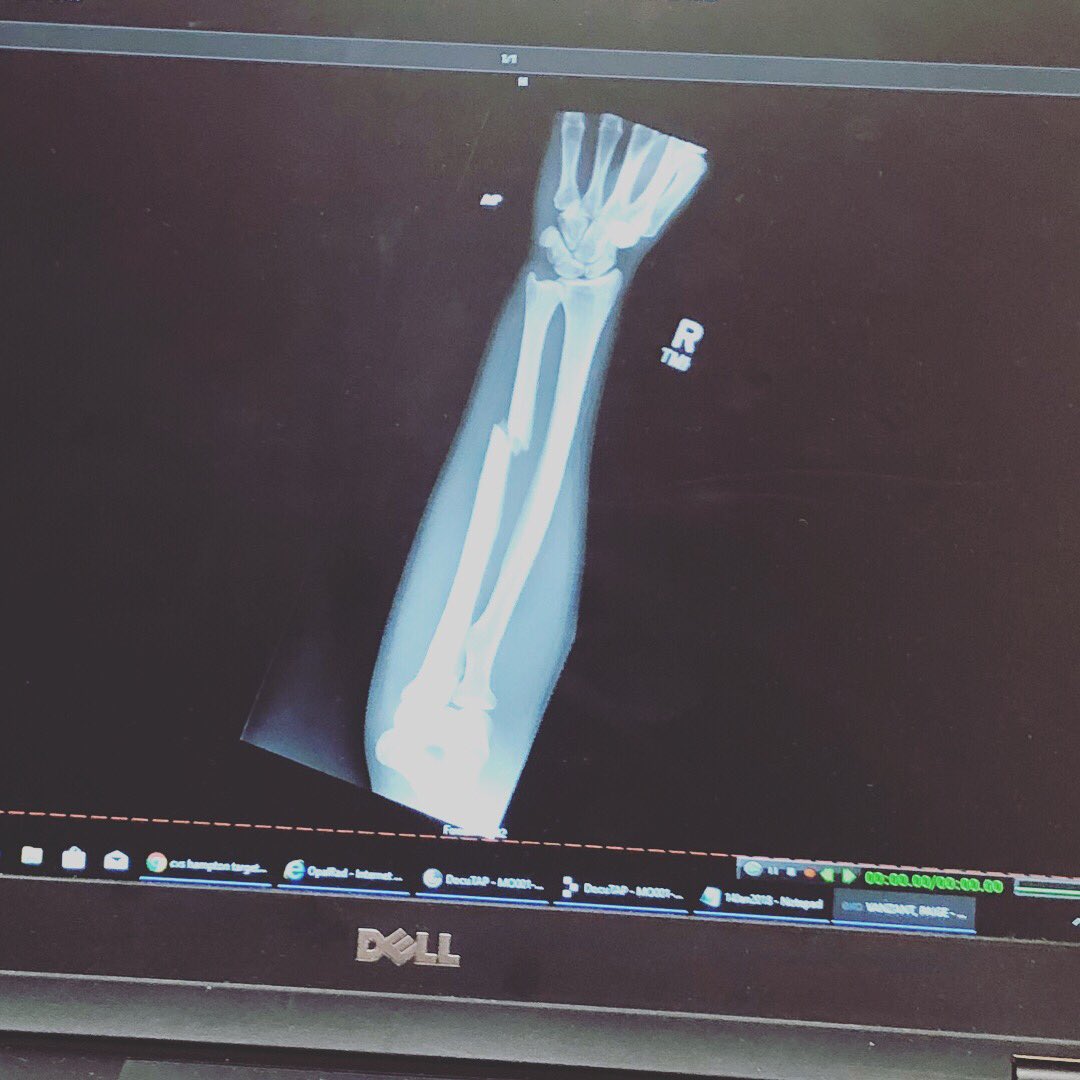

Пейдж Ванзант сломала руку во время боя с Джессикой-Роуз Кларк

Боец наилегчаейшего веса UFC Пейдж Ванзант сломала руку во втором раунде боя против Джессики-Роуз Кларк.

Проклятый бэкфист», – написала Пейдж в инстаграме и выложила фото рентген-снимка.

Перелом случился во время удара «бэкфист» – Ванзант попала предплечьем сопернице в лоб.